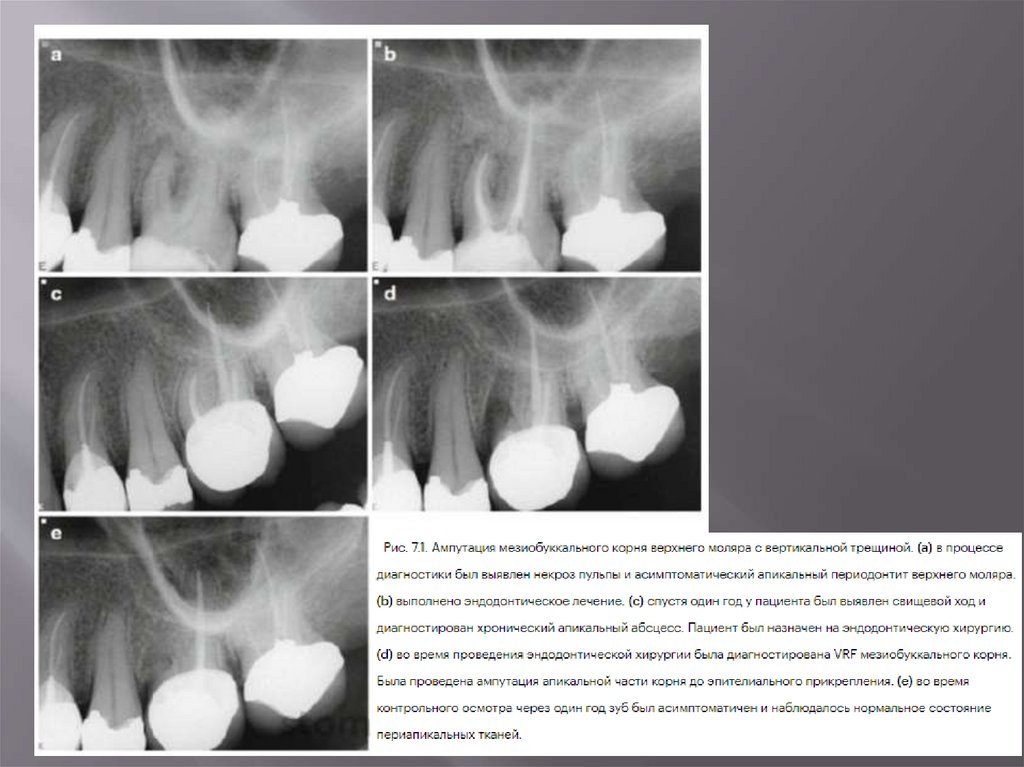

6.7.1. Ампутация, резекция, гемисекция

74